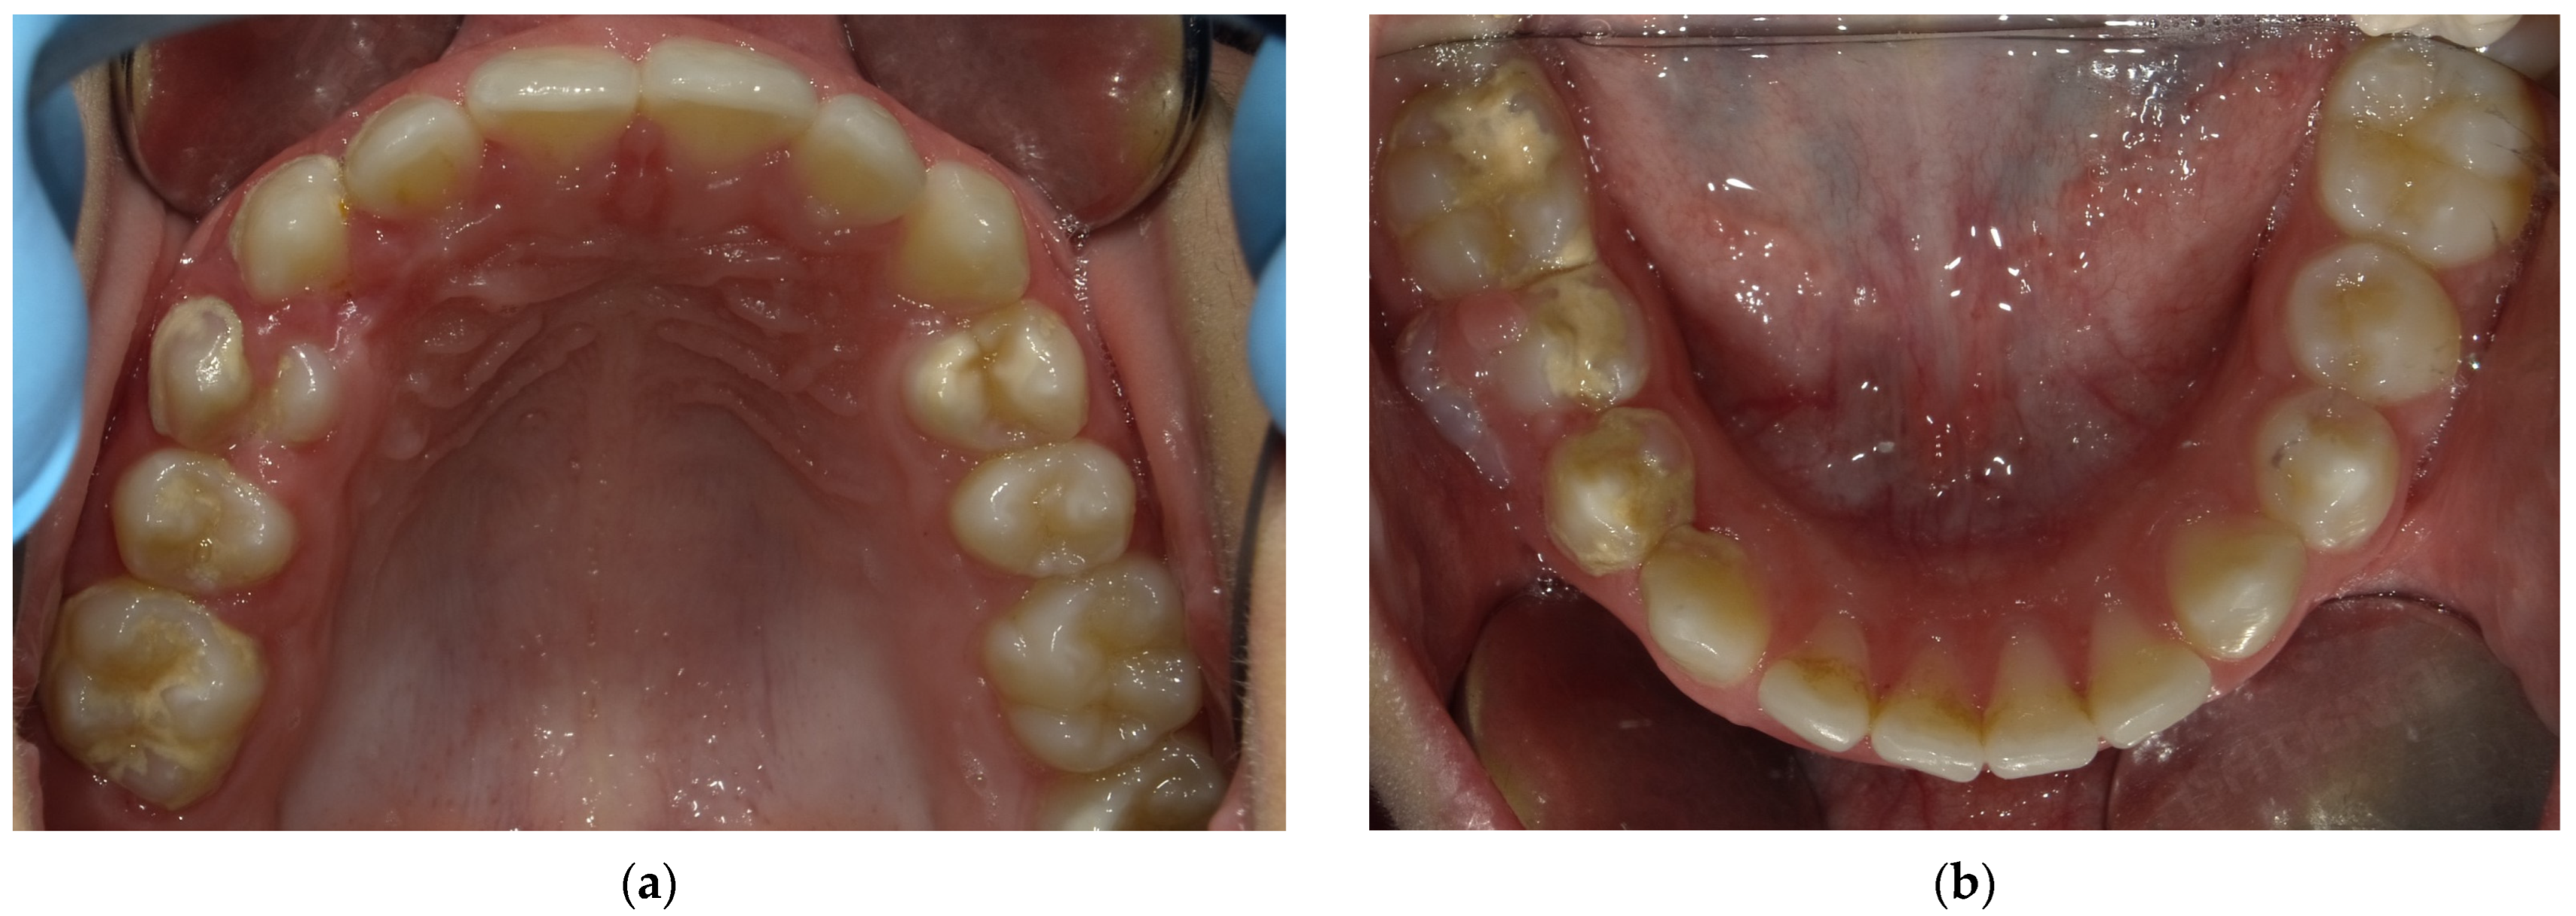

2.5. Follow-Up and Outcomes

3. Results